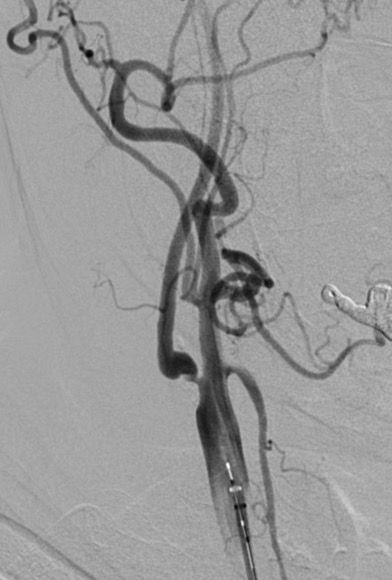

In >2,400 patients with ≥70% asymptomatic carotid stenosis on optimised modern medical therapy, adding carotid stenting almost halved the 4‑year risk of stroke/death vs. medical therapy alone (≈6.0% → 2.8%), with a number needed to treat of ~31 to prevent one primary outcome event over 4 years.

– Revascularisation provides significant additional clinical benefit on top of advanced pharmacological treatment in carefully selected asymptomatic patients.

– The clearest incremental benefit in CREST‑2 was seen with stenting plus best medical therapy, while CEA showed only a modest, statistically non‑significant numerical advantage over medical therapy alone.

– All of this was achieved in expert, high‑volume centres with rigorously credentialed operators and very low peri‑procedural complication rates.

‘Yes—but with the right patient, the right operator, and the right centre.”’